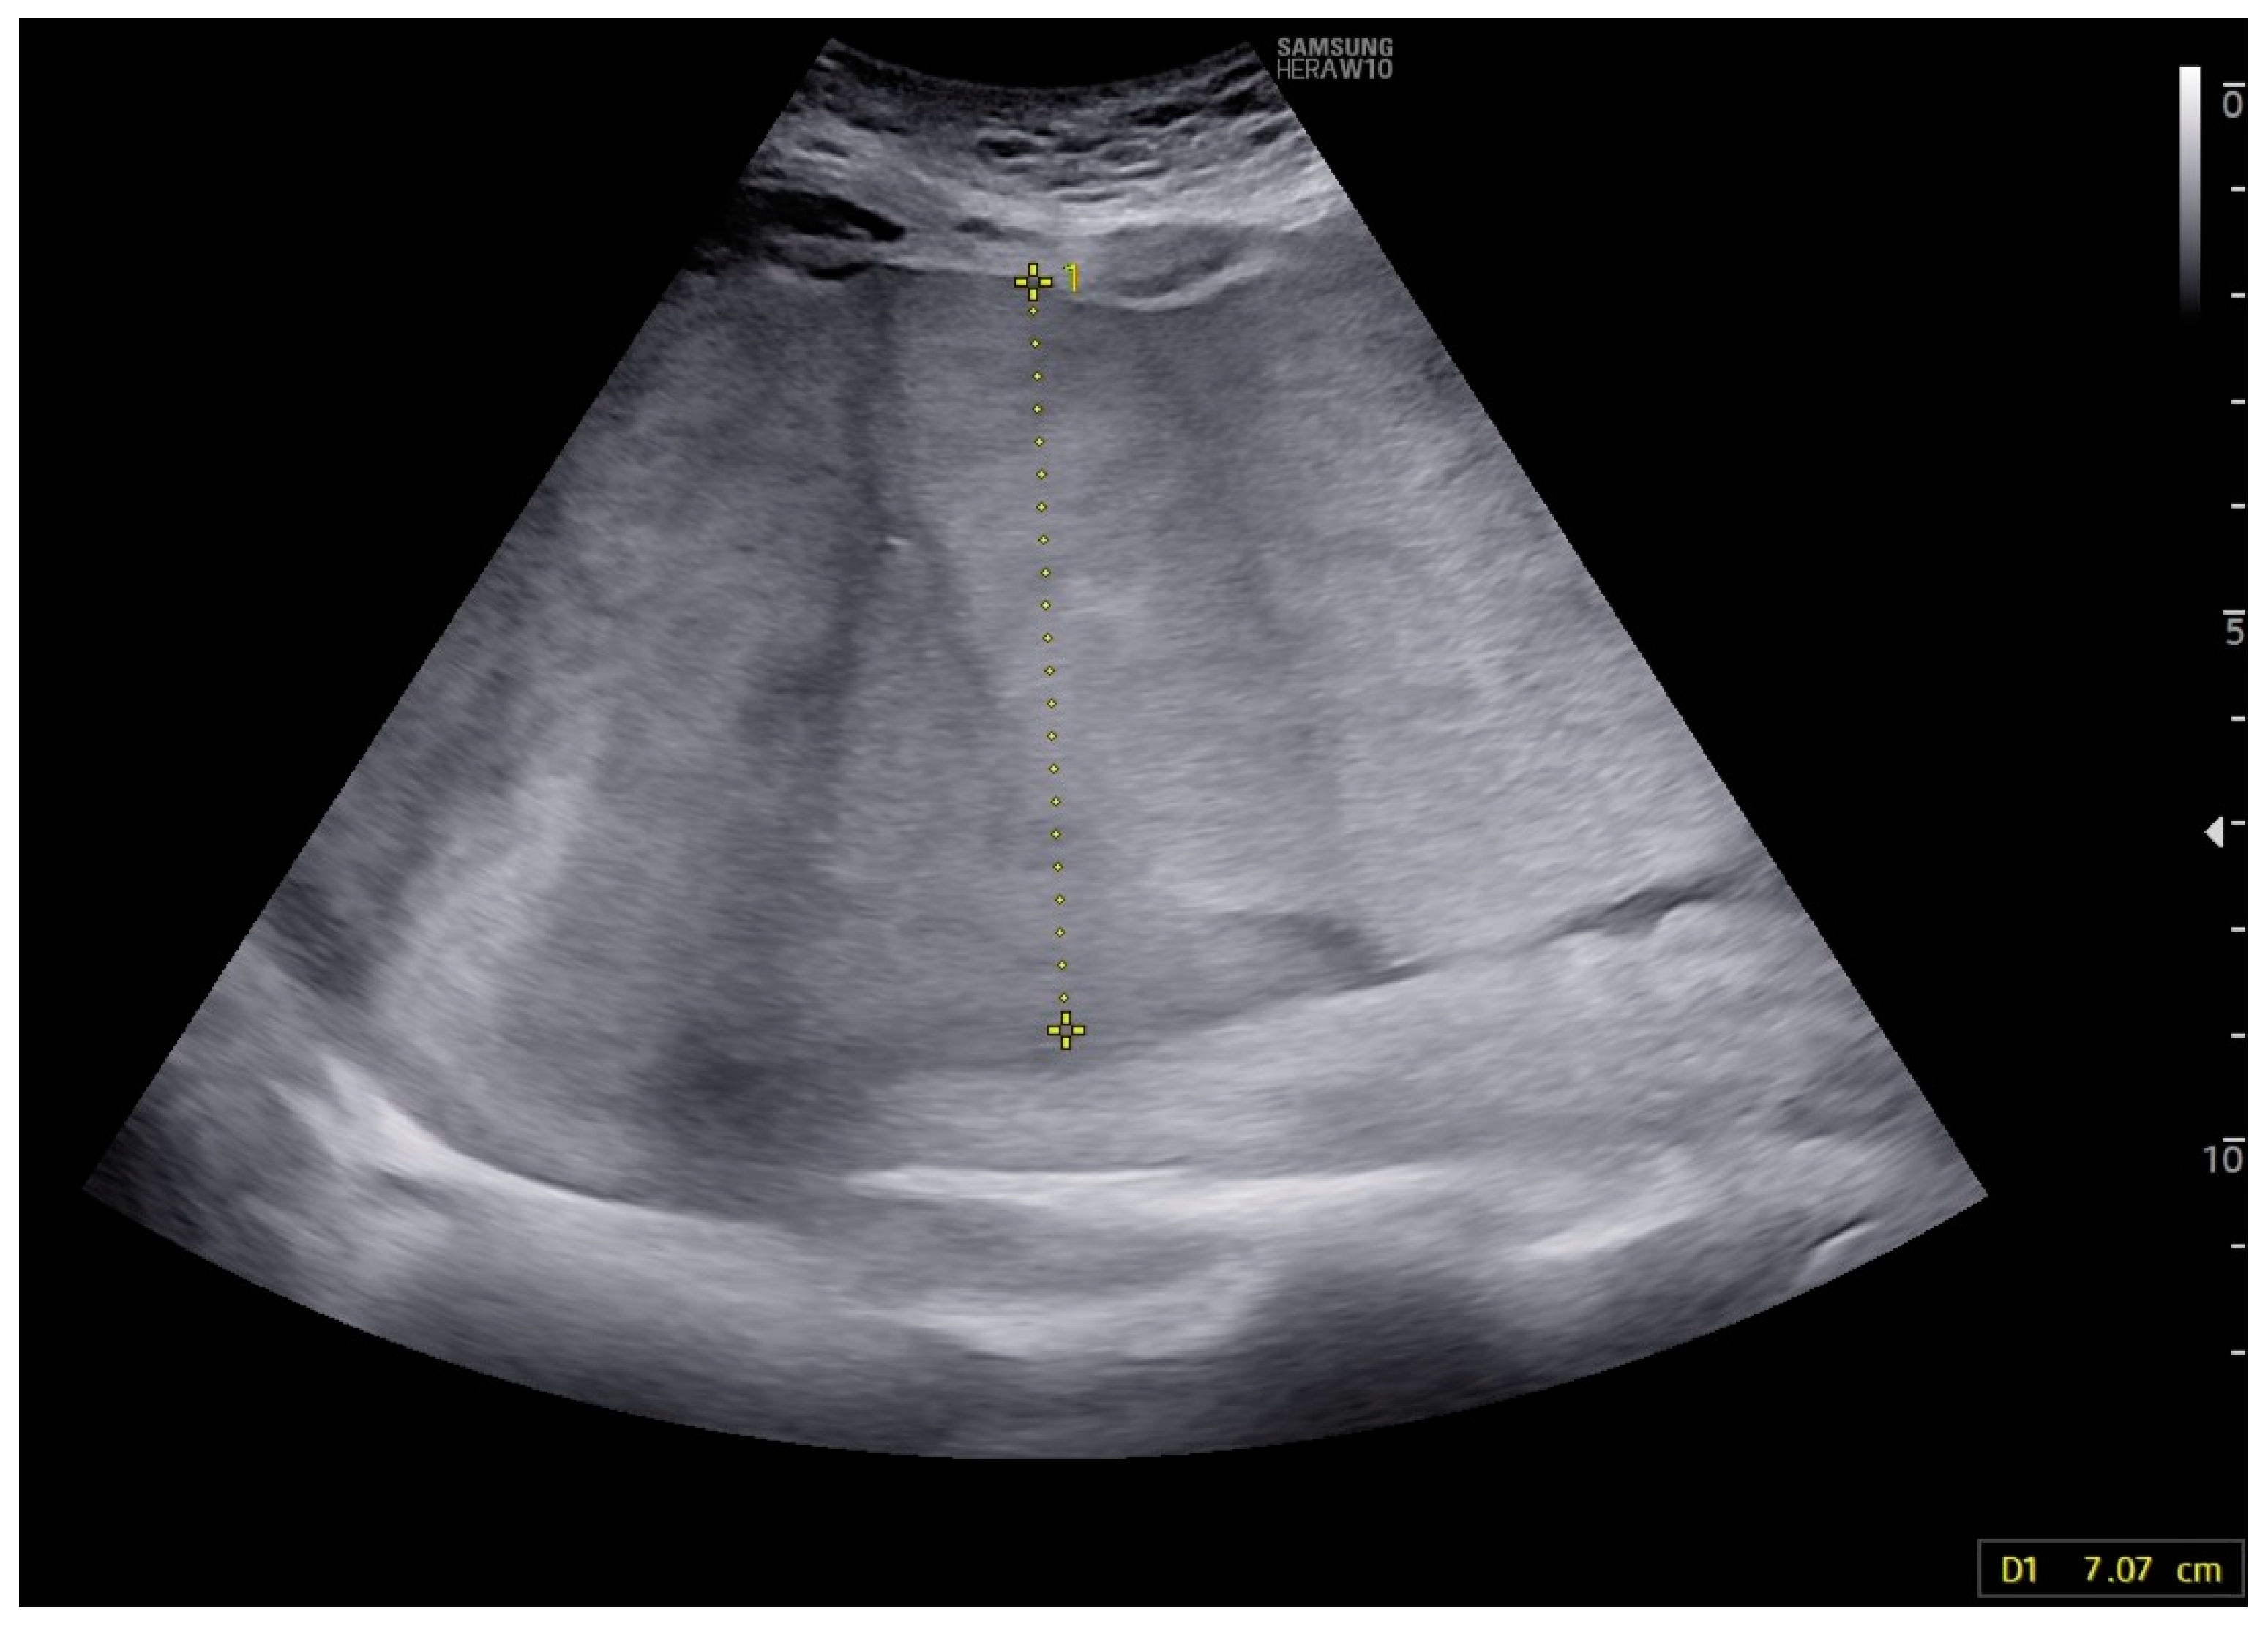

A 32-year-old woman, gravida 2, para 1,0,0, was referred to the hospital due to abnormalities found during a second-trimester ultrasound examination. The findings included placental thickening (Figure 3), subcutaneous tissue edema, ascites, pericardial effusion, and cardiomegaly. The peak systolic velocity of the middle cerebral artery was measured at 78.00 cm/s (2.6 MoM).

Figure 3. Case 5: Thickening of the placenta; after second intrauterine transfusion, 25 weeks of gestation.